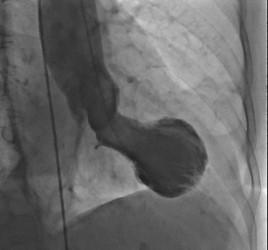

image: This is a Takotsubo heart, showing the typical shape resembling a Japanese octopus trap.

TTS is known as "broken heart" syndrome and is characterised by a sudden temporary weakening of the heart muscles that causes the left ventricle of the heart to balloon out at the bottom while the neck remains narrow, creating a shape resembling a Japanese octopus trap, from which it gets its name. Since this relatively rare condition was first described in 1990, evidence has suggested that it is typically triggered by episodes of severe emotional distress, such as grief, anger or fear, or reactions to happy or joyful events. Patients develop chest pains and breathlessness, and it can lead to heart attacks and death. TTS is more common in women with only 10% of cases occurring in men. [2]